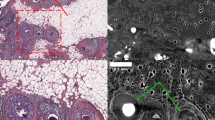

X-ray based analysis suggests perineural infiltration

One of the X-ray data set of a PDAC specimen, taken from a duodenopancreatectomy with R1-status showed a duct with epithelial proliferation and partially papillary architecture located in close proximity to a peripheral nerve. To address the question of whether perineural infiltration was present in the biopsies the tomographic data set was first evaluated in three planes (Fig. 5a). The collagen fibers of the perineural sheath displayed a higher contrast than the nerve fibers per se, and the epithelium of the pancreatic duct and its lumen were clearly visible. In the virtual section planes epithelial cell infiltration of the perineurium was clearly visualized (Fig. 5a, arrow). Therefore, in a second step, both structures, the pancreatic duct and the adjacent peripheral nerve were segmented semi-automatically and stained virtually. Figure 5b shows the spatial topology of the two structures with their connection and intersection. Although the fusion of the duct with nerve tissue was not clearly detectable, the spatial proximity of these structures suggests disintegration of the perineurium. Combining these findings with histological and immunohistochemical results using Movat’s pentachrome stain marking collagenous structures, and anti CK18 stain depicting epithelial cells, supports the assumption of a present perineural infiltration (Fig. 5c).

Representative 2D/3D image analysis to assess suspected perineural tumor cell infiltration. Analysis of the X-ray based data set in all 3 spatial directions revealed potential perineural infiltration by a dysplastic pancreatic duct (yellow arrow), as shown in the virtual sections within the punch biopsy (a). Manual segmentation of nerve (yellow), ductal epithelium (blue), and ductal lumen (green) was performed using virtual sections within the 3D data set (a, left figure). Red arrows in (a) indicate the displayed spatial direction of the virtual 2D tissue section. Spatial representation of the segmented structures within this punch biopsy showed how the dysplastic pancreatic duct and nerve wrapped around each other (b). Subsequent H&E staining on 2D tissue sections (c, left panel), specific immunostaining of the duct epithelium with anti CK-18 antibody (c, middle panel), and visualization of different cellular and extracellular tissue components using Movat’s pentachrome stain (c, right panel) validated the close localization of the perineurium and pancreatic duct